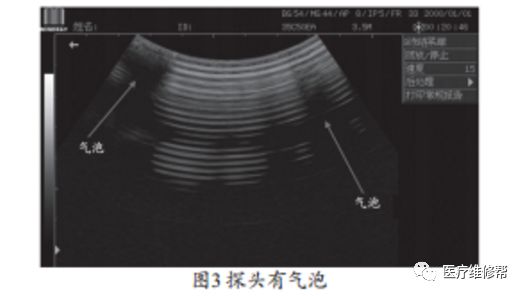

探头有气泡故障现象,见图3。探头起泡后,不论是空载还是打图像都是有明显的黑区,通过挤压探头表面的保护层,可以使气泡在匹配层内发生移动和变化,图像中的黑区也会跟着移动和变化。

声透镜有气泡的维修方案:使用液体硅橡胶作探头声透镜的修补材料以及声透镜层与匹配层之间的粘合材料。用液体硅胶注入脱胶处并赶出气泡,用纱布带用力将探头绑紧放置一天后松开,故障消失。